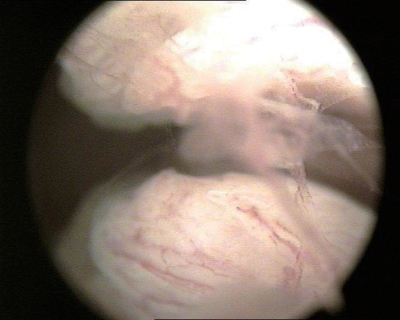

②子宫颈内口:即解剖学内口,呈圆形或椭圆形,内膜比子宫内膜薄,略呈苍白色(图3-3)。